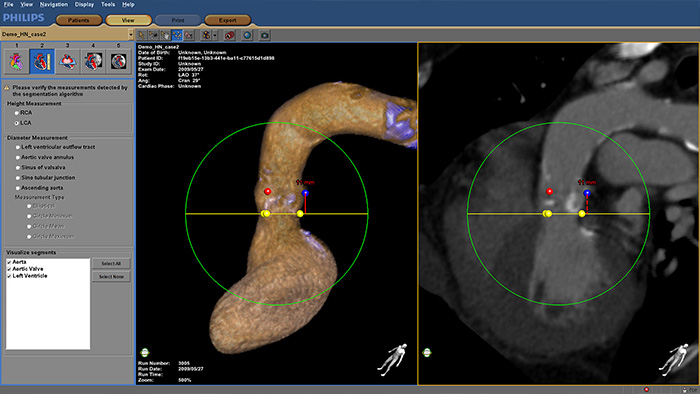

HeartNavigator

Increase confidence and ease during transcatheter aortic valve replacement (TAVR) and other challenging SHD procedures. The immersive user experience is highly automated to simplify planning, device selection and projection angle selection. During procedures, it provides live image guidance to support device positioning.